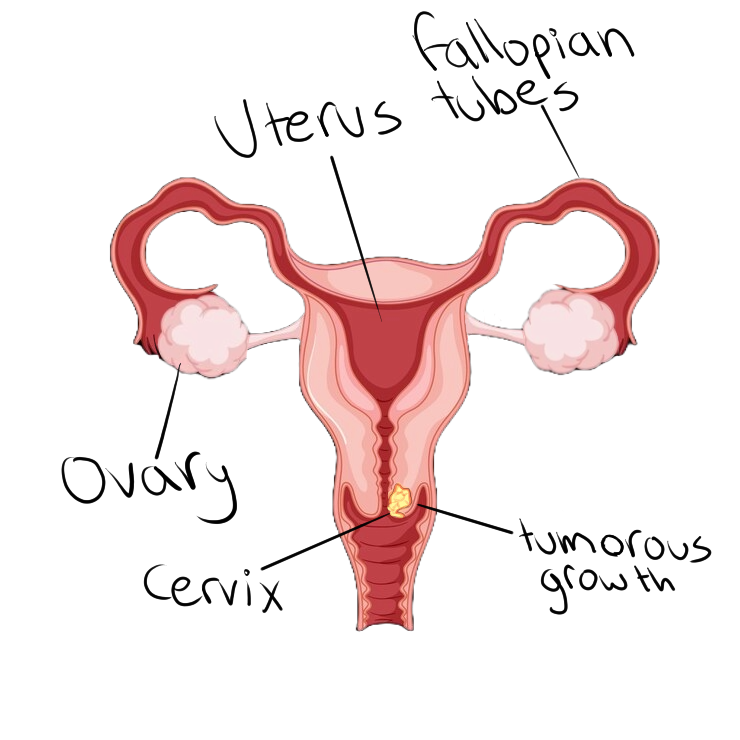

জরায়ুমুখের ক্যান্সার মহিলাদের মধ্যে সবচেয়ে সাধারণ ধরণের ক্যান্সারের মধ্যে একটি। এটি তখন ঘটে যখন জরায়ুর উপরিভাগে ক্যান্সার কোষ বৃদ্ধি পেতে শুরু করে। এটি ছড়িয়ে পড়া শুরু না হওয়া পর্যন্ত লক্ষণগুলি দেখা যায় না। মধ্যবয়সী মহিলাদের মধ্যে জরায়ুমুখের ক্যান্সার সবচেয়ে বেশি হয়।

Cervical cancer is one of the most common types of cancer for women. It occurs when cancer cells begin to grow on the surface of the cervix. Symptoms don't appear until it begins to spread. Middle aged women most commonly receive cervix cancer.